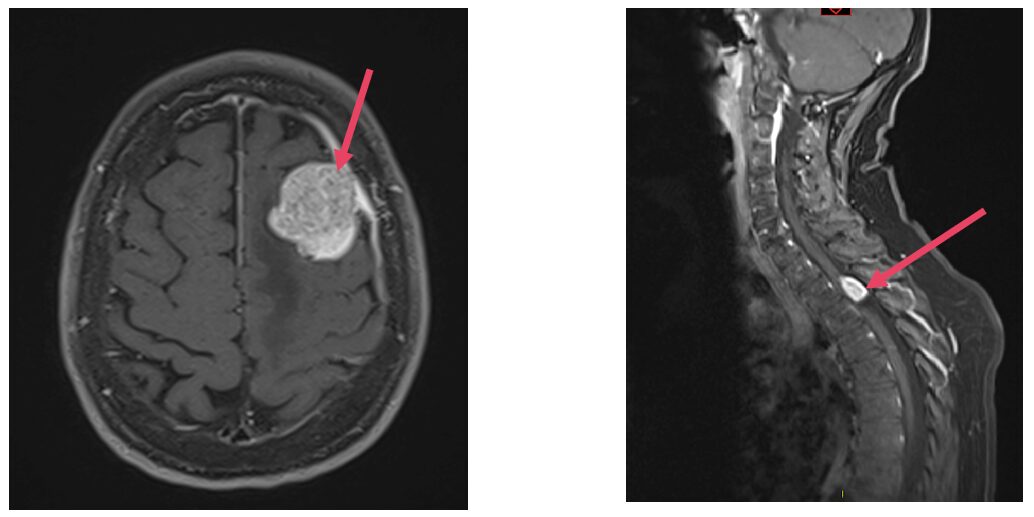

Les méningiomes sont des tumeurs bénignes situées au niveau intracrânien ou rachidien (1).

Les méningiomes peuvent être surveillés de façon radioclinique pendant plusieurs années en fonction de la localisation et de leur évolution.

Le traitement du méningiome peut être une exérèse chirurgicale , si celui-ci est volumineux, responsable de déficit neurologique ou présente un œdème cérébral important.

Les méningiomes sont classés en 3 grades après l’analyse en anatomopathologie en fonction de leur agressivité et de leur rapidité d’évolution.